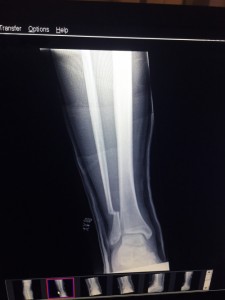

After receiving x-rays following the Gothenburg show that confirmed a broken fibula, the band cancelled dates at the Pinkpop Festival in the Netherlands (6/14) and St. Gallen, Switzerland (6/16). Grohl flew to London for further x-rays and an MRI followed by an operation on Monday (6/15) in which a plate held in place by six screws was attached to the bone.